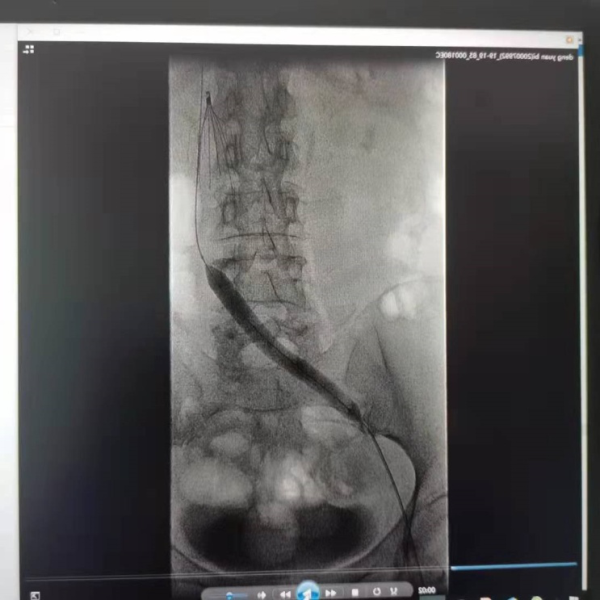

在手术过程中,马永恩医生发现患者存在左髂静脉压迫综合征(这是左下肢深静脉血栓形成的罪魁祸首),与邓女士沟通病情后后行左髂静脉球囊扩张及支架植入术,手术完成 48小时后复查血管造影,残余血栓几乎完全消散,遂撤出溶栓导管。患者经过观察,未出现任何异常,肿胀的大腿也明显恢复,患者顺利出院。